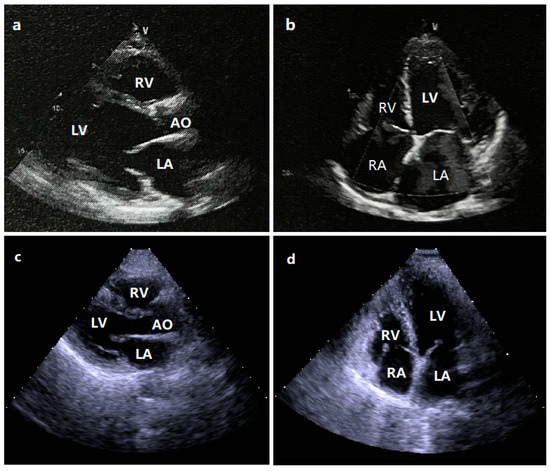

3.1. Phenotypic Information of the Studied Family Members Suffering from DCM